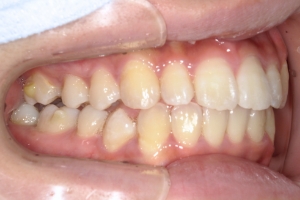

BEFORE

治療前

下の前歯が上あごの歯ぐきに当たるほど噛み合わせが深く、そのことが原因で上顎歯列の正中にすき間(正中離開)が生じていました。部分矯正ですき間を無理やり閉じても、噛み合わせが深いままでは治療後の再発リスクが高くなります。そのため全体矯正で奥歯の噛み合わせを整え、噛み合わせを浅くしつつ前歯を並べました。正中離開は戻りやすい傾向があるので、再発を防ぐため固定式リテーナーを推奨しています。